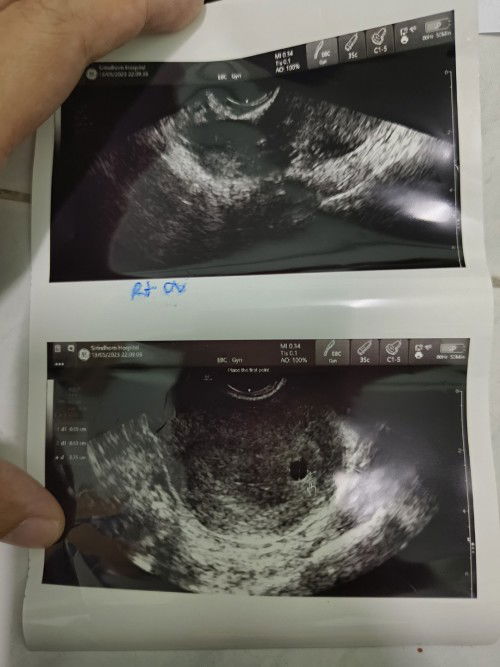

มีใครเคยเป็นแบบนี้ไหมคะมีมูกเลือดออกปวดท้องบีบๆไปซาวผ่านช่องคลอดดูหมอบอกว่าเจอแต่ถุงตั้งครรภ์ไม่เจอตัวอ่อน เป็นได้3กรณี 1.แท้งสมบูรณ์ 2.ท้องลม 3.ท้องยังอ่อนมากๆหมอนัดไปอีกที2อาทิตย์ไปซาวดูใหม่ กังวลมากๆเลยกลัวเสียเขาไปมากๆ ใครเคยเป็นขอคำแนะนำหน่อยนะคะตอนนี้เคลียดมากๆ #ท้องที่2ค่ะ#ขอบคุณล่วงหน้านะคะ